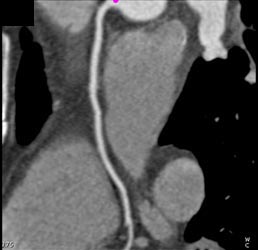

Plaque in LAD